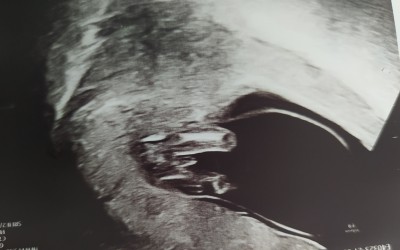

benjm oğluşum olacakmış kızlar. Secde eder gibi duruyo surekli

Gebelik haftası 14+3

Hayırlı olsun. Bu bacagının arası mı? Uzaktan ultrason var mı acaba vücudu net görünen

Bi tek bunu verdi Dr bacak arası dedi ama sanırım yan duruyo popo ayaklar Bi yerde gozuluyo